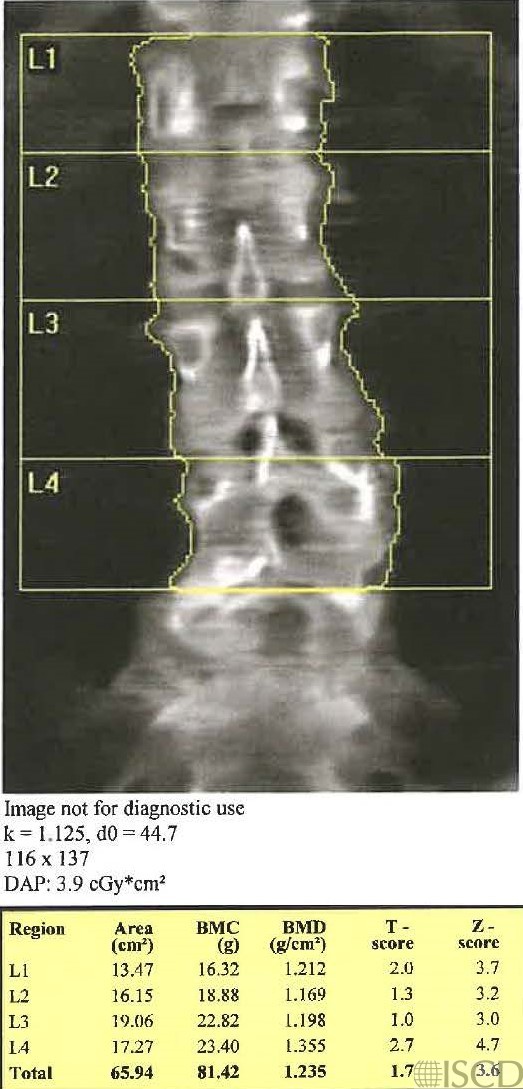

The same patient was scanned within 5 minutes with the legs down and then the legs up on the block. This scan has the legs down.

This scan has the legs up on the block. There is not a statistically significant difference in L1-L4 BMD using the 95% confidence intervals for the scanner.